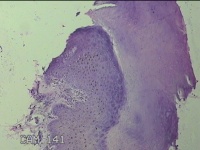

右拇指远端结节

性别

男

年龄

37岁

临床诊断

皮脂腺囊肿

一般病史

发现右拇指远端结节2年余。

标本名称

大体所见

灰白粉红色组织1.8x1.2x00.8cm一个,表面带梭形皮肤1.3x0.7cm,皮下见结节1.2x0.8cm一个,切开结节呈实性,切面灰白粉红色,质中。

图1